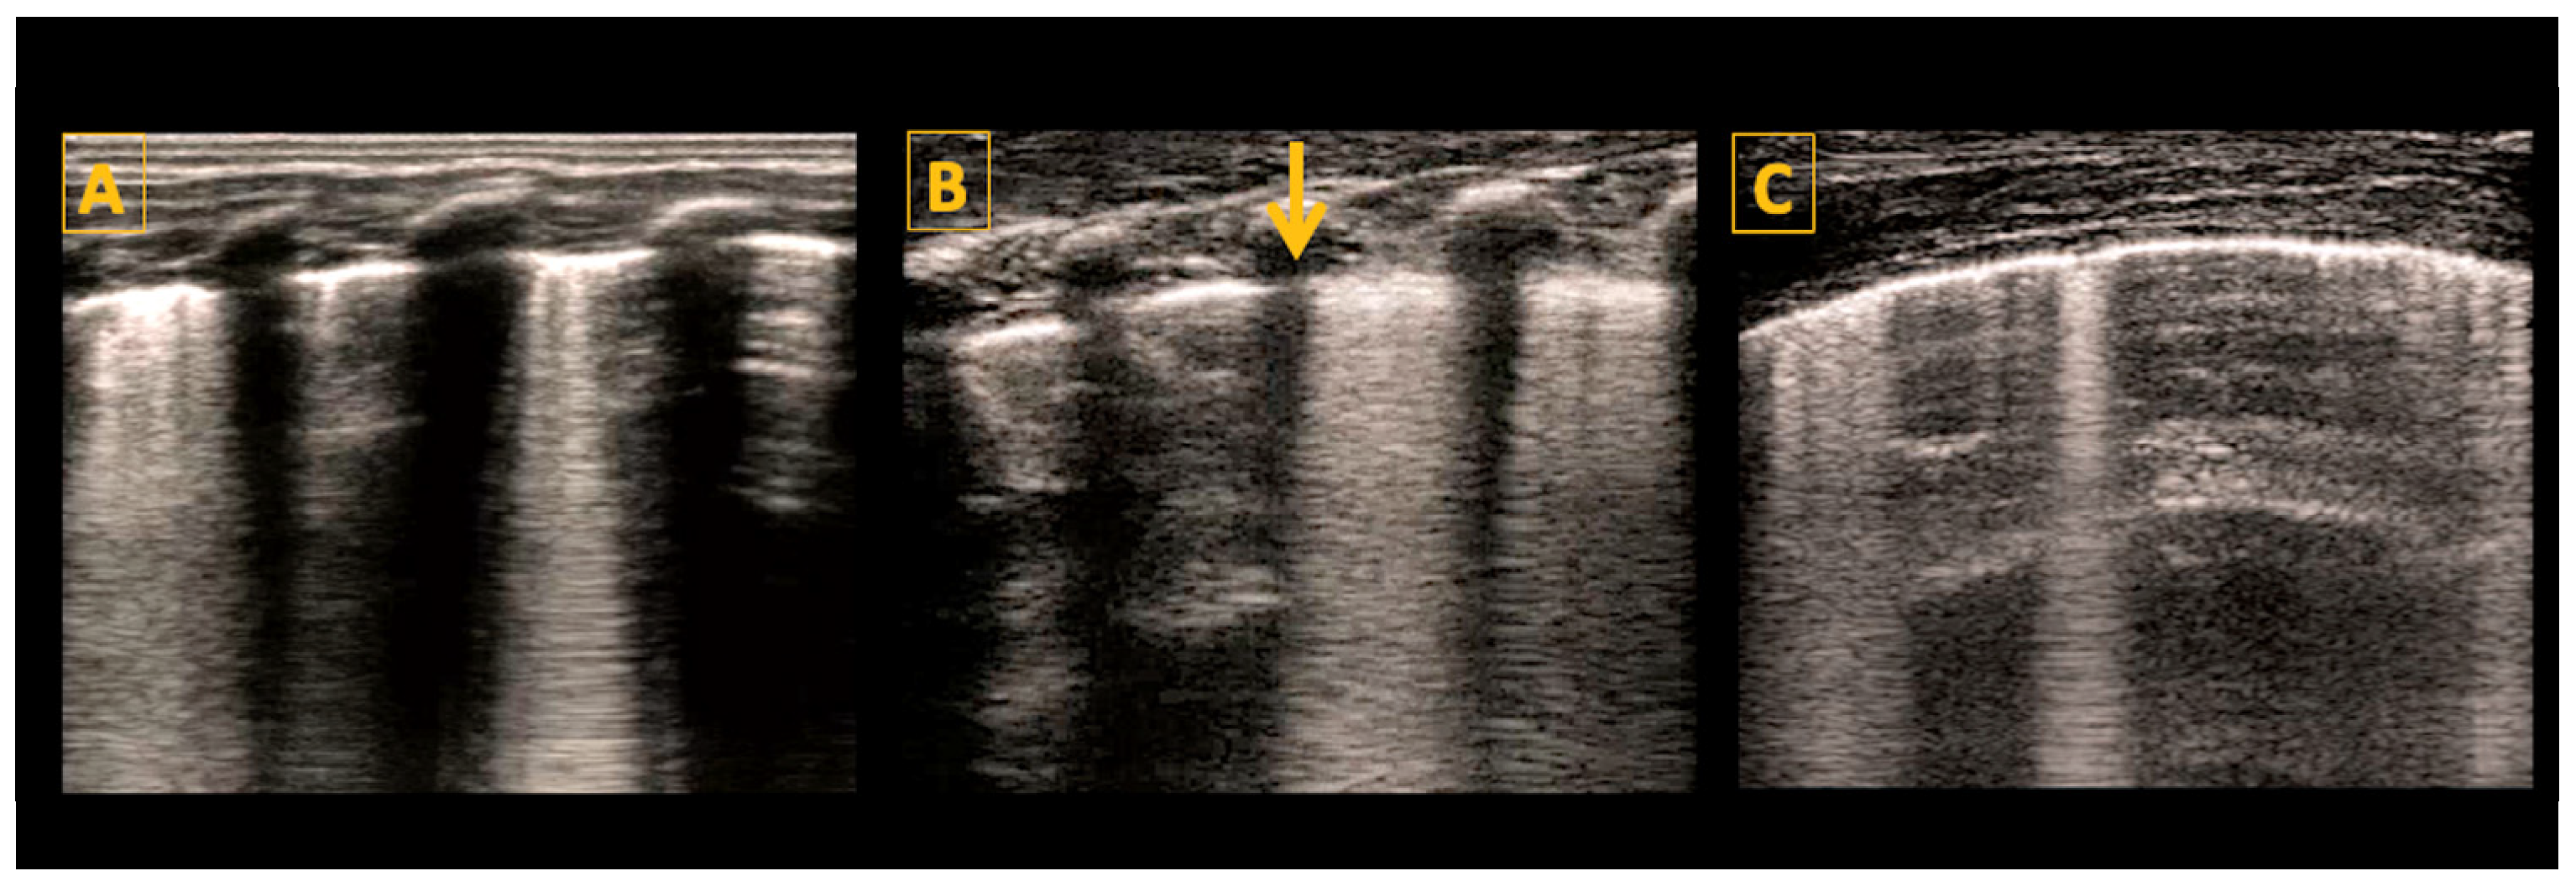

5.5. Consolidations

- Pneumothorax

- Liu, J.; Kurepa, D.; Feletti, F.; Alonso-Ojembarrena, A.; Lovrenski, J.; Copetti, R.; Sorantin, E.; Rodriguez-Fanjul, J.; Katti, K.; Aliverti, A.; et al. International Expert Consensus and Recommendations for Neonatal Pneumothorax Ultrasound Diagnosis and Ultrasound-guided Thoracentesis Procedure. J. Vis. Exp. JoVE 2020, e60836. [Google Scholar] [CrossRef]

- Liu, J.; Chi, J.-H.; Ren, X.-L.; Li, J.; Chen, Y.-J.; Lu, Z.-L.; Liu, Y.; Fu, W.; Xia, R.-M. Lung ultrasonography to diagnose pneumothorax of the newborn. Am. J. Emerg. Med. 2017, 35, 1298–1302. [Google Scholar] [CrossRef] [PubMed]

- Lichtenstein, D.; Mezière, G.; Biderman, P.; Gepner, A. The ‘lung point’: An ultrasound sign specific to pneumothorax. Intensive Care Med. 2000, 26, 1434–1440. [Google Scholar] [CrossRef] [PubMed]